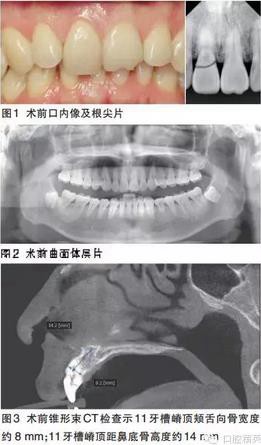

牙體:11冠折,斷面位于齦下,松動Ⅲ度,牙齦有觸痛,21切1/3部分缺損,無明顯松動。牙列:完整恒牙列。咬合:前牙區(qū)內(nèi)傾型深覆Ⅱ度。牙周:未見明顯牙石,牙齦無明顯紅腫,個(gè)別牙面可見少量黃褐色色素沉積。黏膜:唇緣線對稱,唇紅色澤自然,無皸裂,口角區(qū)黏膜無糜爛。頜面部:面部左右對稱,無腫脹、疼痛,面部比例協(xié)調(diào),下頜運(yùn)動正常。開口度:正常。

根尖片示11牙頸部可見折裂影像。

曲面體層片示38、48低位埋伏阻生。

錐形束CT示11牙根唇側(cè)骨壁較薄約0.5~1mm;11牙槽嵴頂頰舌向骨寬度約8mm;11牙槽嵴頂距鼻底骨高度約14mm;11牙槽嵴長軸與牙冠長軸方向夾角約34°。